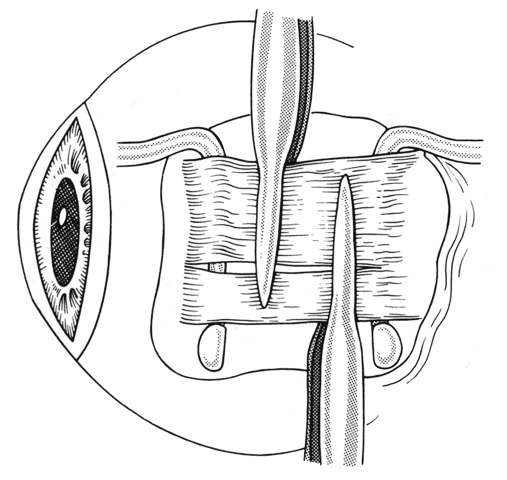

In some situations, a portion of a horizontal rectus may be left at the insertion site (Figs. 9 and 10). The muscle is usually split at the time of the initial procedure, and this can cause a shift of the distribution of force at the insertion and cause vertical misalignment. The pattern of the strabismus and the details of the previous surgery should provide clues to the problem and allow a logical approach for correcting the vertical deviation. Suspicions should be confirmed by careful dissection and exploration of the region of the muscle insertion. The importance of careful evaluation and elimination of mechanical restrictions cannot be overemphasized.4,10

Fig. 9. Residual exotropia or hypertropia can occur if a portion of the lateral rectus muscle is not recessed with the first procedure. To prevent this, care must be taken to incorporate all portions of the tendon when recessing an extraocular muscle.

Fig. 10. The pole test, or sweeping a Stevens muscle hook anterior to the insertion, will ensure that the entire tendon is on the Jameson muscle hook.